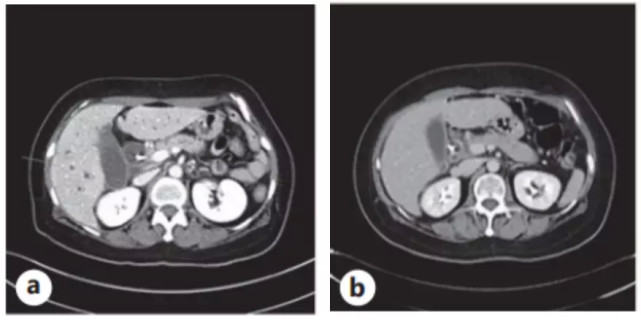

入院后化验总胆红素为 6.3 mg/dL,AST 190 IU/L,ALT 287 IU/L,ALP 441 IU/L,CA 19-9 8840 U/mL。增强CT检查发现胰腺有直径1.4 cm 的肿物,进一步的MRI发现了多处肝转移。超声内镜活检确诊为胰腺导管腺癌伴多发肝转移。

患者以吉西他滨联合白蛋白结合型紫杉醇作为一线化疗方案,两个周期后,病情稳定,但四个周期后进行病情评估,疾病进展了。此时化验,AST 22 IU/L,ALT 8 IU/L,ALP 59 IU/L,CA 19-9 8961 U/mL。

期间化验CA 19-9显著下降(图1),2020年1月,CT显示仅存在体积缩小的胰腺原发肿块(图2b),MRI提示除胰腺原发肿瘤外,没有肝转移及其他肿块,可选择手术治疗,但患者及家属因经济等原因拒绝了。为降低治疗费用,患者增加了化疗的间隔,并在2020年2月26日之后患者失访,两个月没有回院。

图2. (a)脂质体伊立替康治疗前,胰腺癌的原发灶和多发性肝转移。(b)脂质体伊立替康五个月后,原发灶体积缩小,肝转移消失